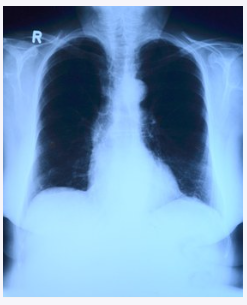

1. 폐암

폐암은 한 마디로 폐에 생긴 악성 종양을 말하는데요. 폐 자체에서 암이 발병할 수도 있지만 다른 곳에 있던 암이 전이되어 폐에서 발전하는 경우도 있습니다.

현재까지 알려진 바에 의하면 폐암의 가장 큰 원인은 흡연으로 나타나 있습니다. 폐암 환자의 약 70%가 흡연으로 인해 발생한다고 하니, 흡연이 주된 원인 중 하나라고 할 수 있습니다.